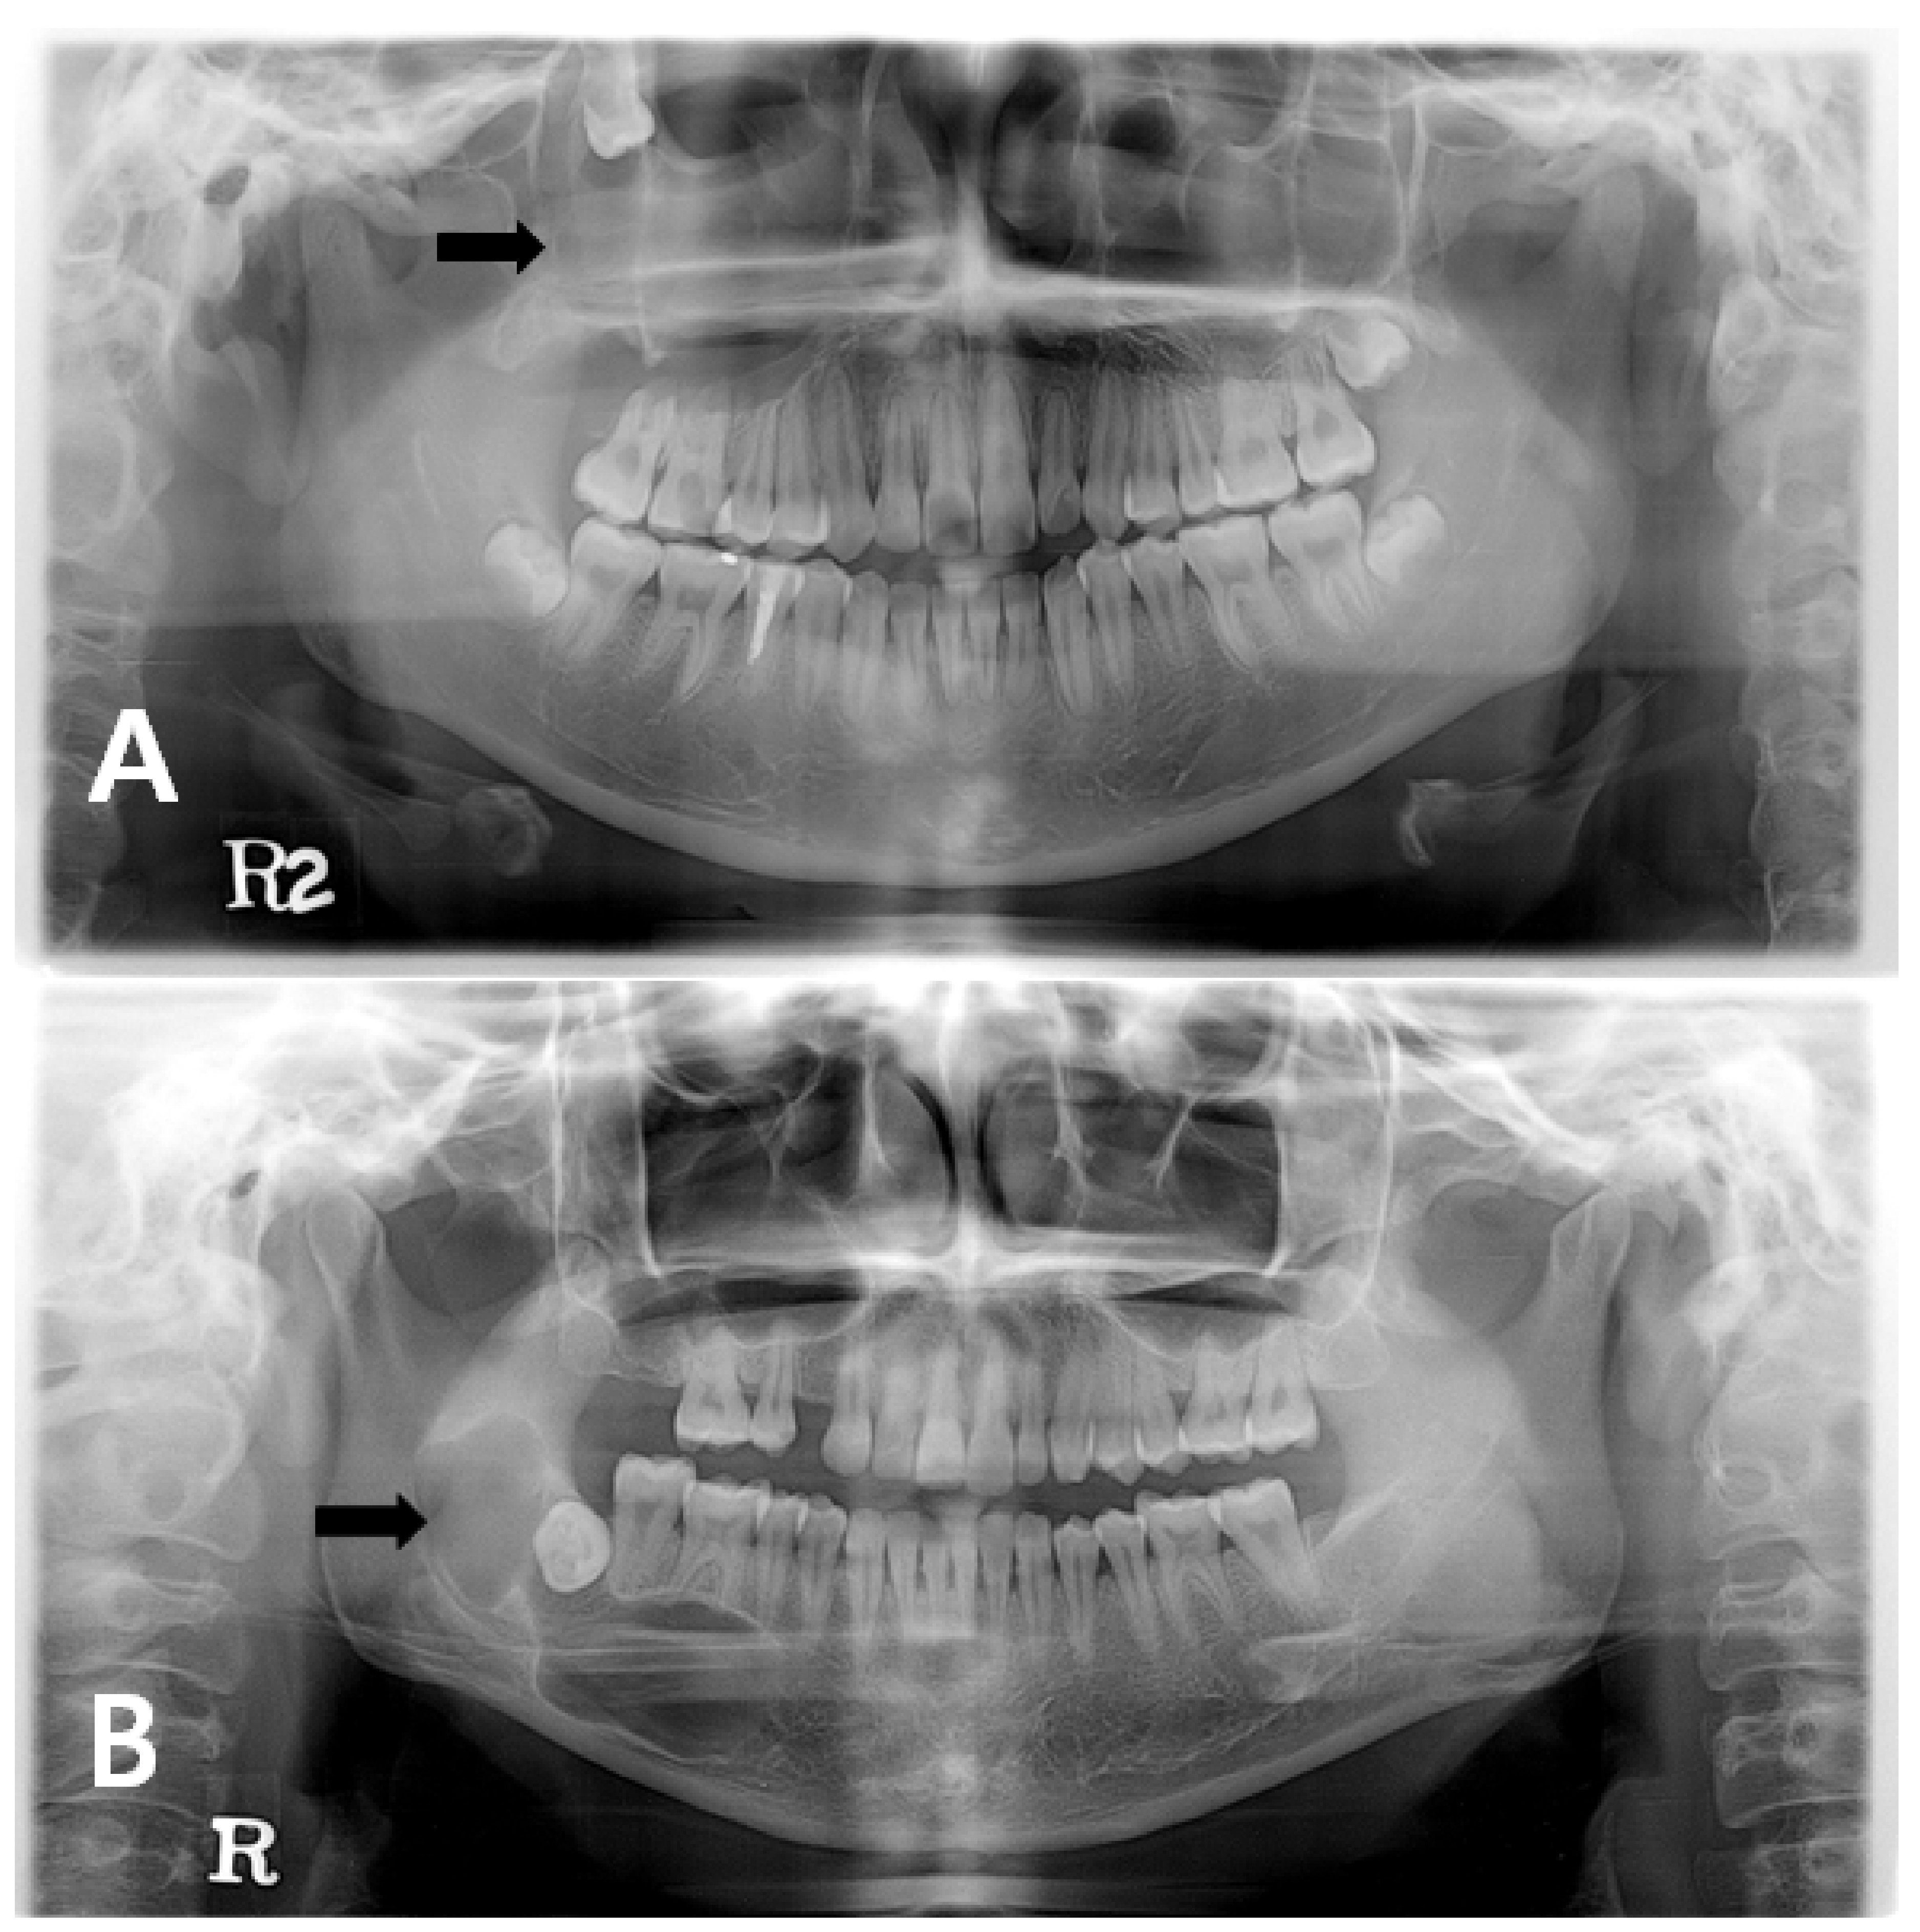

Differential diagnosis Imaging differential considerations include.

There was a recurrence of the cyst in a few months and. Odontogenic keratocyst okc or keratocystic odontogenic tumor kcot. Large odontogenic keratocysts sometimes are treated initially by cystotomy and insertion of a drainage tube which can promote shrinkage of the lesion and fibrous thickening of the cyst wall before subsequent total removal.

In the WHOIARC classification of head and neck pathology this clinical entity had been known for years as the odontogenic. Dentigerous cyst both dentigerous cysts and odontogenic keratocysts can be positioned pericoronally dentigerous cysts tend to attach at the cemento-enamel junction of teeth radicular cyst. Comprehensive review with recent updates on who classification 2017.

Surgical Removal of Odontogenic Keratocyst. Odontogenic keratocysts OKCs are benign intraosseous odontogenic lesions that have a locally aggressive behavior and exhibit a high recurrence rate after the treatment. Odontogenic keratocysts can initially be treated with incisional biopsy and decompression by installing a polyethylene drain to allow subsequent reduction of the cystic cavity size resulting in thickening of the capsule which allows a later easy removal withapparently lower relapse rate waldron.

The excision of the overlying mucosa. Odontogenic keratocyst is one of the most aggressive odontogenic cysts with a high recurrence rate this was explained histopathologically as it typically shows a thin friable wall which is often difficult to enucleate from the bone in one piece and have small satellite cysts within the fibrous wall. Immediate mandibular reconstruction with a corticocancellous iliac crest bone graft.

Recurrence Of Odontogenic Keratocyst Okc In Relation To Cortical Download Scientific Diagram